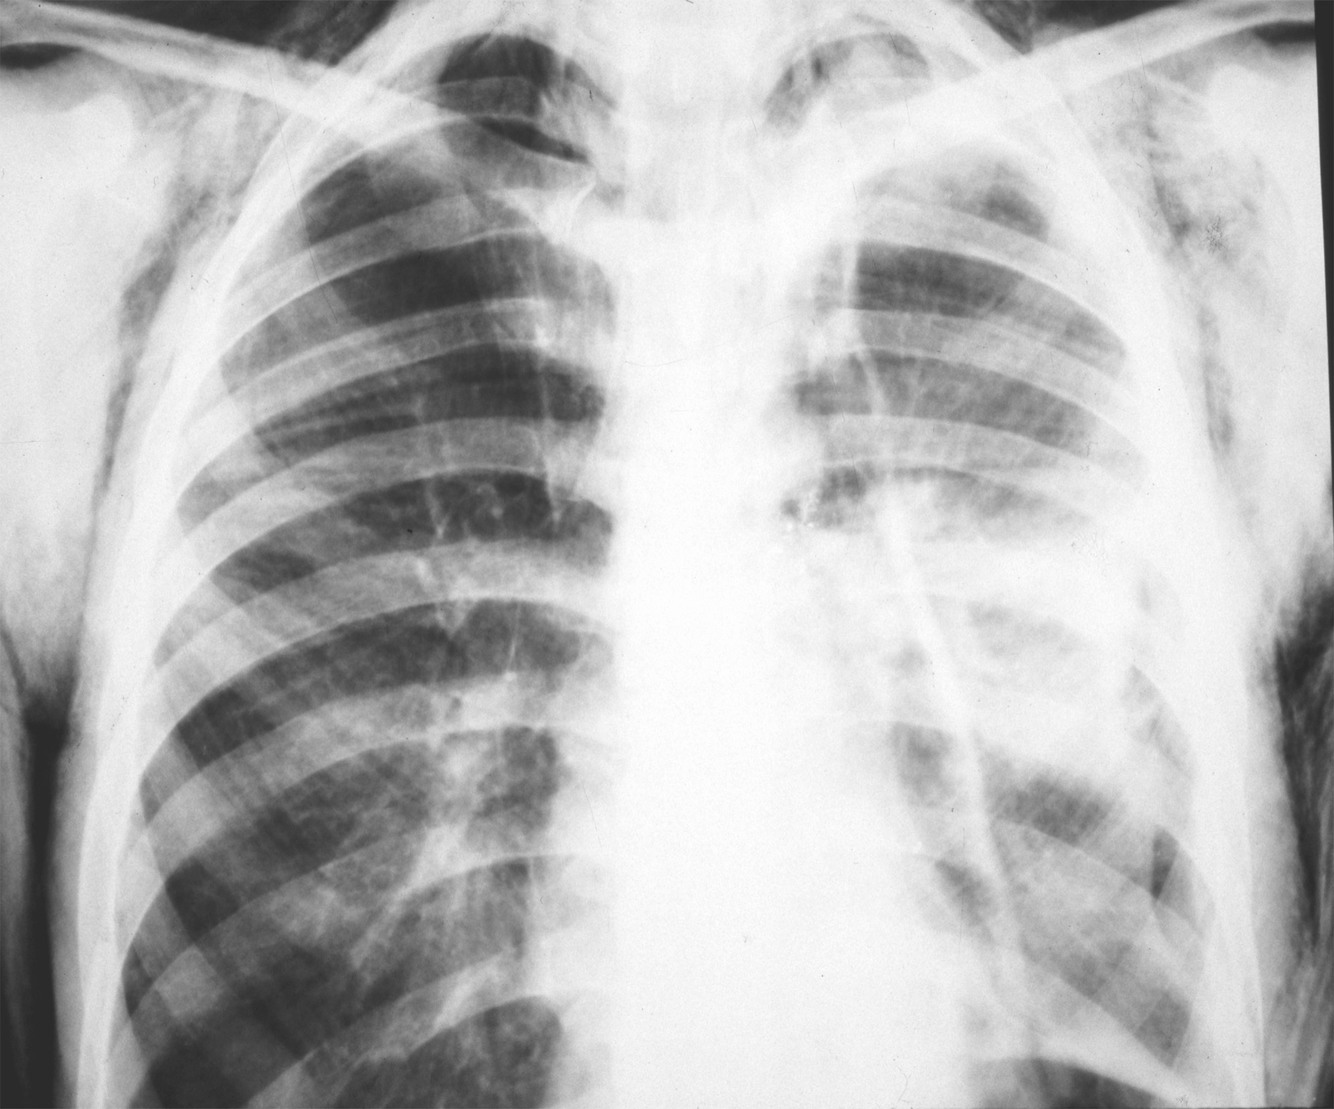

Paciente vitima de trauma de tórax apresenta-se na emergencia com MV diminuidos ou abolidos, hipertimpanismo, desvio da traqueia para o lado contralateral, turgencia jugular e hipotensão…

Diagnóstico, exame de imagem, conduta imediata e definitiva?

PNEUMOTÓRAX HIPERTENSIVO

Não fazer exame de imagem. Diagnóstico é clínico

Conduta imediata

Toracocentese de alívio no 4-5o EIC anterior a linha axilar media

*na criança continua no 2o EIC

Conduta definitiva

Drenagem em selo d’água (toracostomia) no 5o EIC anterior a linha axilar media